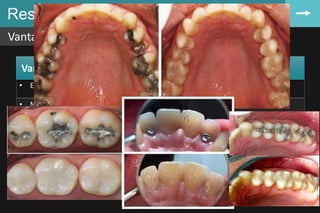

Resina composta

Vantagens e desvantagens

81

Vantagens Resinas quimicamente ativadas (autopolimerizáveis)